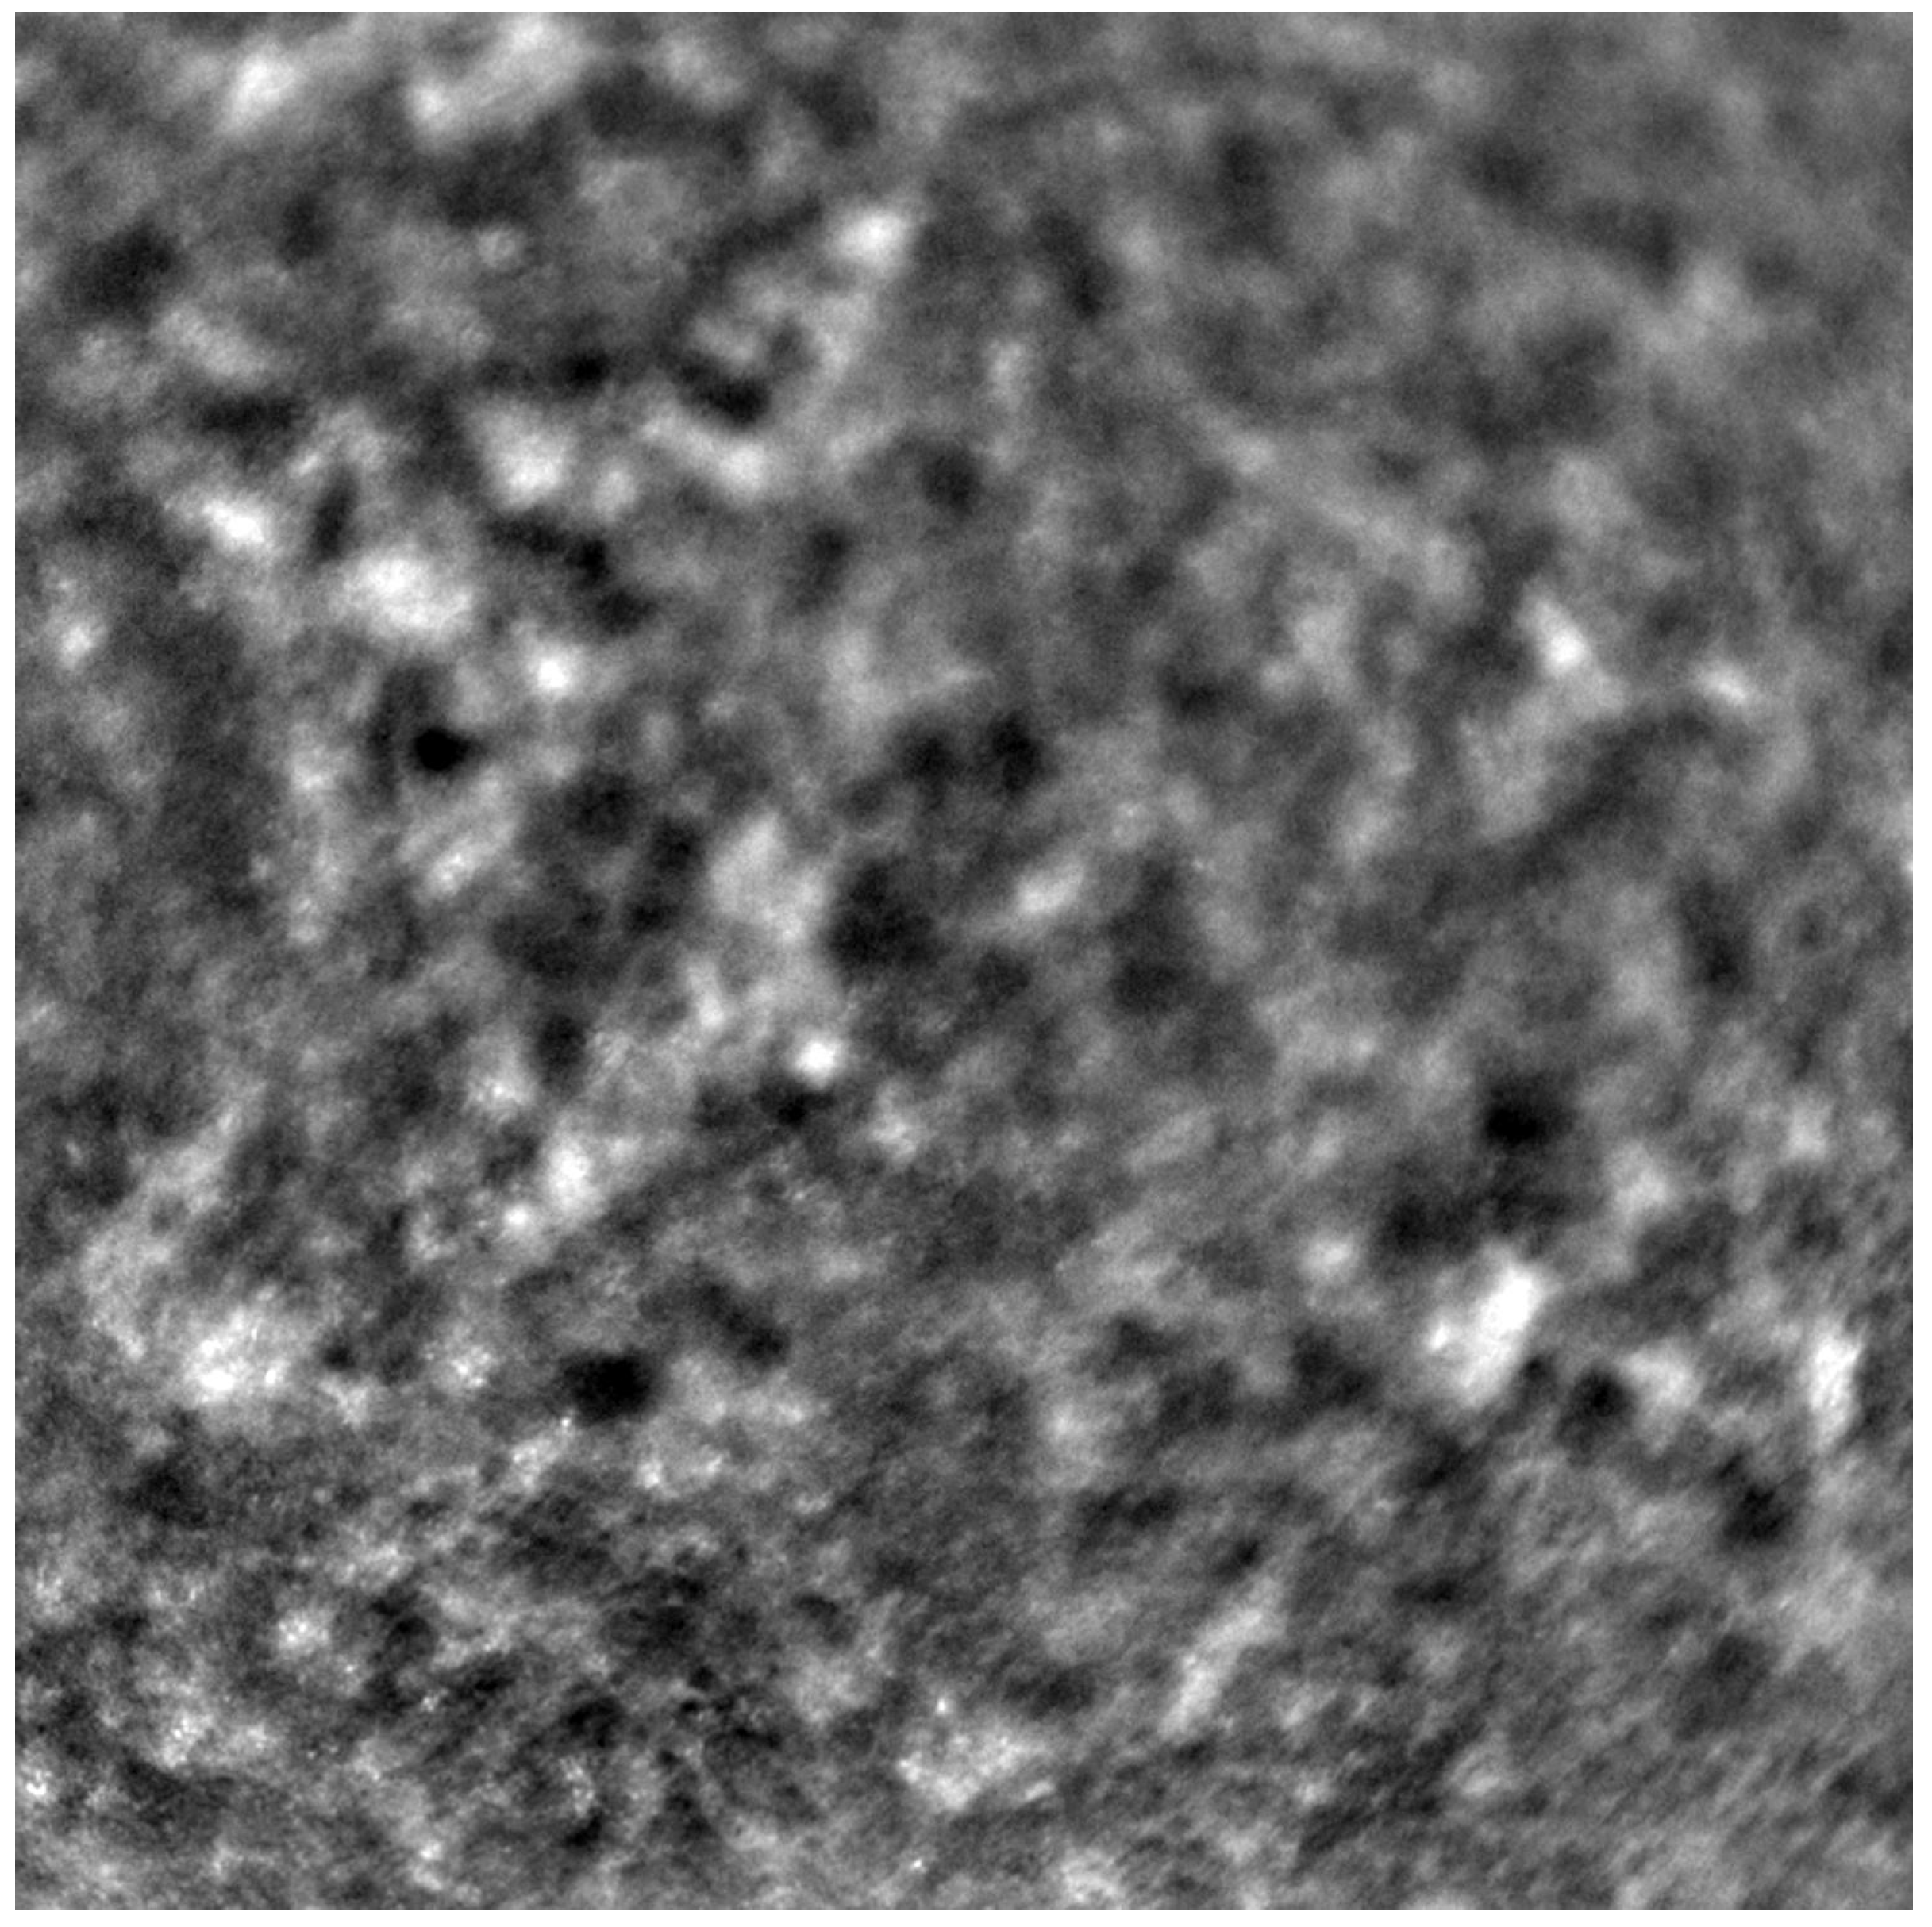

Adaptive optics retinal images depicting a healthy eye, CD, CRD, and STGD are presented in Figure 1, Figure 2, Figure 3 and Figure 4.

Figure 1 depicts the photoreceptor mosaic in a healthy eye. The image is taken paracentrally (2 ° superiorly) due to the limited ability of foveal image acquisition by Rtx™ [17]. By changing the focus point, the quality of an acquired image provides the assessment of photoreceptor parameters in parafoveal cones. The aberration and noise found in Figure 2, Figure 3 and Figure 4 are considered to be the result of poor fixation in eyes with impaired central vision in the course of macular disease. This issue has been addressed in our study. The assessment of factors predisposing for obtaining inadequate image quality was taken into consideration further in this article.

Cone mosaic disruption is an abnormality typical of IRDs. The cone and rod spacing is increased in IRDs compared to healthy retinas [18]. Additionally, poor image quality, likely resulting from inadequate fixation in eyes with low visual acuity, is a problem that, in some cases, makes image acquisition impossible [19,20]. In STGD, as well as in other IRDs, the “dark spaces” depicting areas of disrupted cone structure and abnormal cone reflectance have been described [21,22].

Figure 2. An adaptive optics image of the photoreceptors of an eye afflicted by cone dystrophy (Rtx1™, Imagine Eyes, France). Observe the cone disruption throughout the image with “dark spaces” apparent within the cone mosaic across different areas of the image.